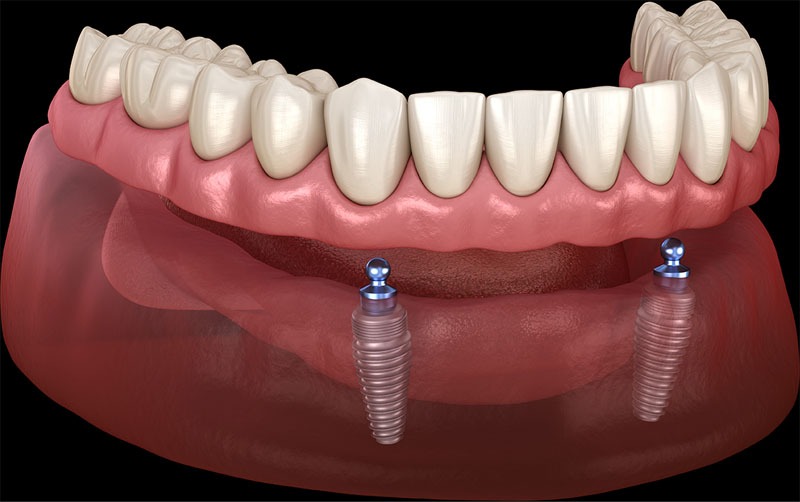

Elevate your dental care journey with our membership program, specifically designed for patients seeking teeth implants. As a member, you’ll benefit from reduced pricing on implant procedures, priority scheduling for consultations and treatments, and continuous follow-up care to ensure the best outcomes. Join today to access top-tier dental implant services and enhance your smile with confidence.